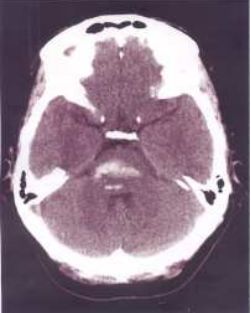

74.44歲女性有酗酒習慣,某日熬夜喝酒之後突然口語不清,吞嚥困難,因此被送到急診求治;患者未注射對比劑的電腦斷層掃描檢查如圖,最可能的診斷為何?(A)小腦梗塞(B)小腦出血(C)腦幹梗塞(D)腦幹出血